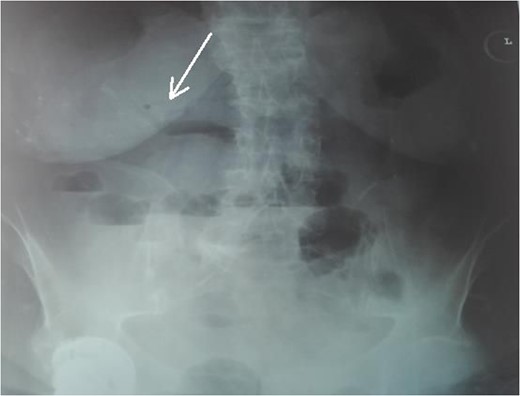

An 87-year-female patient was admitted to emergency department complaining about vomiting for the past 7 days with mild abdominal pain. The patient was hemodynamically stable, had sluggish bowel sounds and soft abdominal wall with mild tenderness. The patient also suffered from atrial fibrillation, heart failure, myelodysplastic syndrome, hiatus hernia and cholelithiasis. The findings of the laboratory tests were unremarkable. Plain chest and abdominal radiograms revealed hiatus hernia with gastric dilation (Fig. 1), a few air-fluid levels and pneumobilia, with delineation of extrahepatic and intrahepatic bile ducts by air (Fig. 2). A nasogastric tube was inserted, which drained biliary content. An abdominal computed tomography (CT) scan revealed the presence of air in the intrahepatic bile ducts, free air and leakage of oral contrast agent in the hepatic hilum and subhepatic space and an impacted gallstone in the third portion of the duodenum (Figs 3 and 4). The diagnosis of cholecystoenteric fistula and proximal gallstone ileus was set.

Abdominal radiogram. The arrow shows the air in the bile ducts.